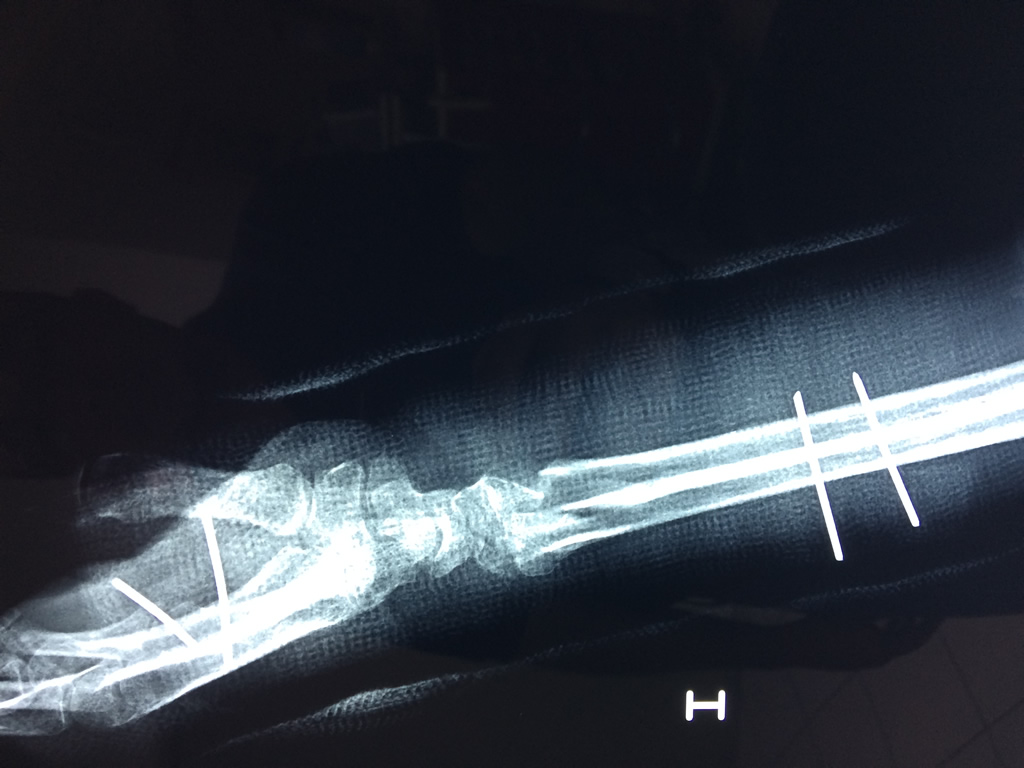

Cirugías de Húmero - Cirugías de Muñecas y Manos

Los procedimientos más comunes en cirugía de la mano son aquellos destinados a reparar traumatismos, incluyendo lesiones de tendones, nervios, vasos sanguíneos, y articulaciones; huesos fracturados; y quemaduras, cortes, y otros daños de la piel.